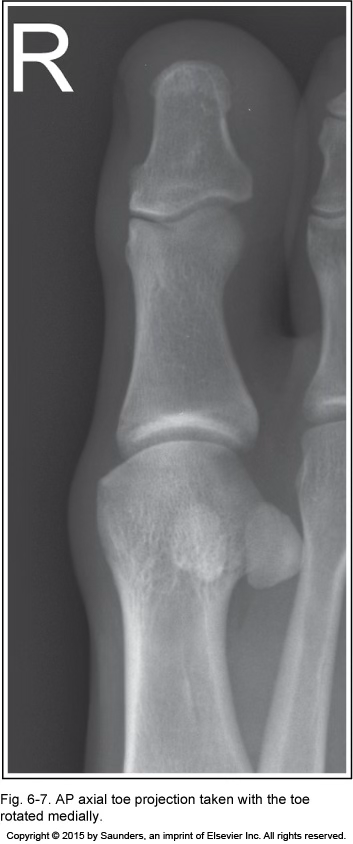

AP axial toe

rotated medially